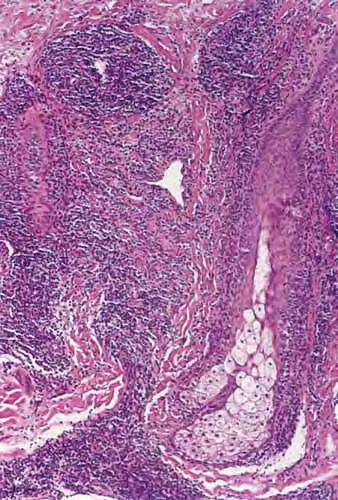

Jessner's lymphocytic infiltrate = الارتشاح اللمفاوي لجسنير